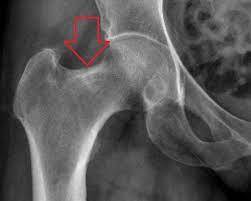

Pincer lesion

acetabulum extends out too far and “pincers” the femoral head causing FAI

CAM lesion

“knuckle” of bone coming out of the femoral neck seen in FAI